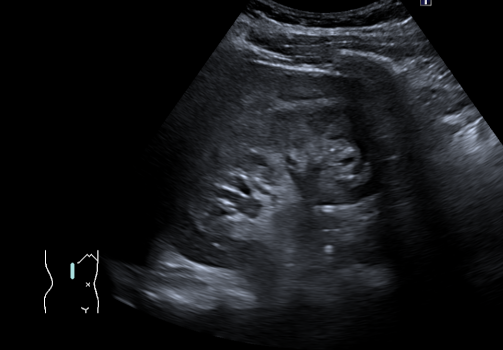

In diesem Fallbericht beschreiben wir einen 17-jährigen Patienten, der mit rez. ausgeprägten Koliken in unserer Abteilung vorstellig wurde. Initial erfolgte bei Hydronephrose °III und pos. Steinanamnese des Vaters eine CT-Abdomen nativ, welche bereits den V.a. einen retrocavalen Harnleiter rechts ergab. Eine Szintigraphie bestätigte eine urodynamisch relevante Obstruktion bei ausgeglichener Nierenfunktions. Bei Symptomatik erfolgte eine retrograde Ureteropyelographie mit JJ-Einlage. Im weiteren Verlauf wurde noch eine MRT-Angiographie durchgeführt, welche den Befund eindeutig bestätigte. Daraufhin erfolgte am 10.11.2025 die daVinci-assistierte Ureterureterostomie rechts in Linksseitenlage. Hierfür wurden 4 Arbeitstrokare und ein Kameratrokar verwendet. Die Gesamtoperationszeit lag bei 181 min, die reine Konsolenzeit bei ca. 100 min. Intraoperativ erfolgte ein JJ-Wechsel. Die Anastomose erfolgte mit einer 4.0 Quill-Naht in fortlaufender Technik. Der Blutverlust lag bei ca. 20 ml. Postoperativ waren die Schmerzen mit Novalgin gut beherrschbar. Die Entlassung erfolgte am 5. postoperativen Tag nach DK-Entfernung.

Abbildung 1 [Abb. 1], Abbildung 2 [Abb. 2], Abbildung 3 [Abb. 3], Abbildung 4 [Abb. 4], Abbildung 5 [Abb. 5], Abbildung 6 [Abb. 6], Abbildung 7 [Abb. 7], Abbildung 8 [Abb. 8], Abbildung 9 [Abb. 9], Abbildung 10 [Abb. 10]